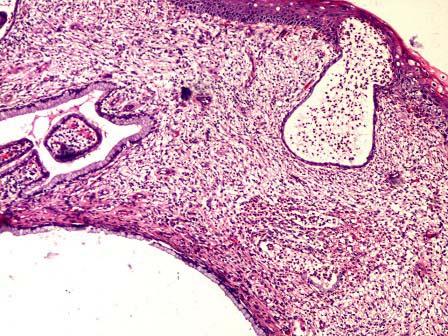

问题 30岁,白带量多,宫颈见多个腺体开口,可见囊肿,取宫颈组织送检,显微镜下所见如图,最适合的诊断为 ( )

选项 A.宫颈鳞状上皮化生 B.宫颈肠上皮化生 C.宫颈纳氏囊肿 D.鳞状上皮包涵囊肿 E.腺瘤样增生

答案 C